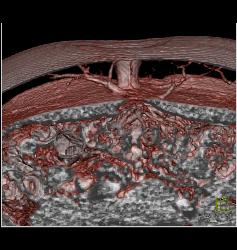

DIEP Flap Planning in 3D